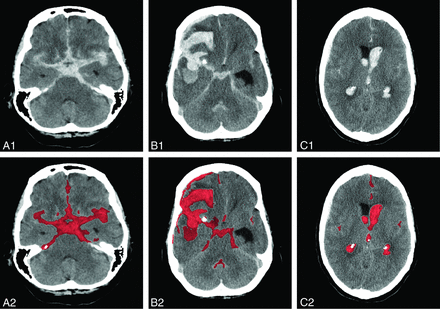

For the volume analysis, generally the first CT scan (all 5-mm sections) after the aSAH ictus was used. Only in case of a rebleeding within 24 hours and before treatment was the CT scan after rebleeding used because of the larger blood volume. All CT scans were anonymized before assessment (H.A.M. and I.A.Z.) and were thereafter assessed for the appropriateness for automated quantification (I.A.Z.). The TBV (in milliliters) was automatically quantified (Fig 1), and the quality of the automatic segmentation was evaluated by using ITK-SNAP, Version 2.4.0 (www.itksnap.org) (I.A.Z.).13

Examples of SAH bleeding patterns on CT (upper), with corresponding segmentations in red as provided by the automatic quantification method (lower).10 A, SAH with blood in both Sylvian fissures. B, SAH with the presence of IPH. C, SAH with the presence of IVH.

All CT scans were inspected for the presence of intraparenchymal hematoma (IPH) and/or intraventricular hematoma (IVH) (I.A.Z.). The presence or absence of IPH and IVH was scored dichotomously because it was not possible to measure blood volume in separate locations with our automated quantification method. The differentiation between a blood clot in the Sylvian fissure and an IPH was made on the initial CTA (I.A.Z.).14 All estimates of blood volume and blood location were performed blinded to the presence or absence of DCI.